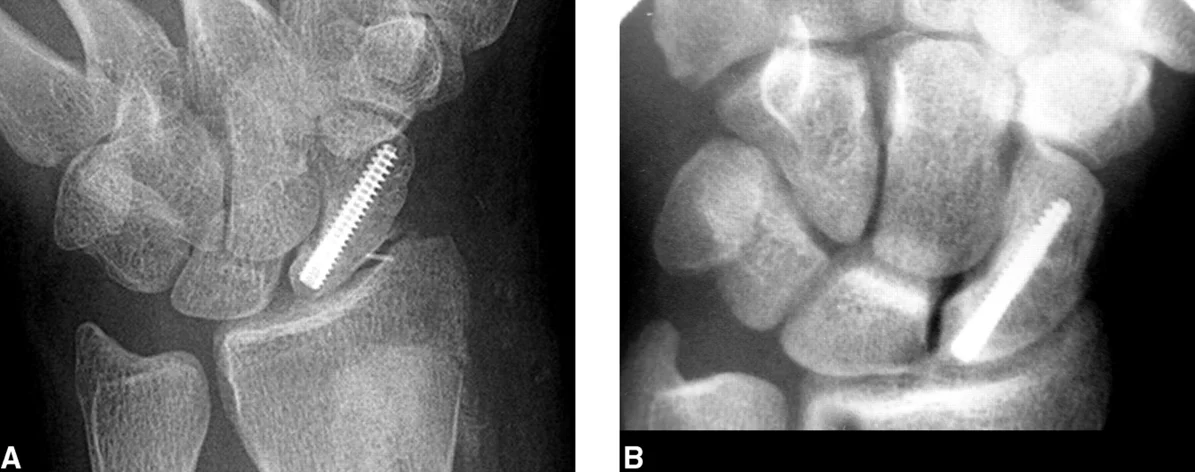

Displaced and proximal fractures

- Internal fixation with special screw